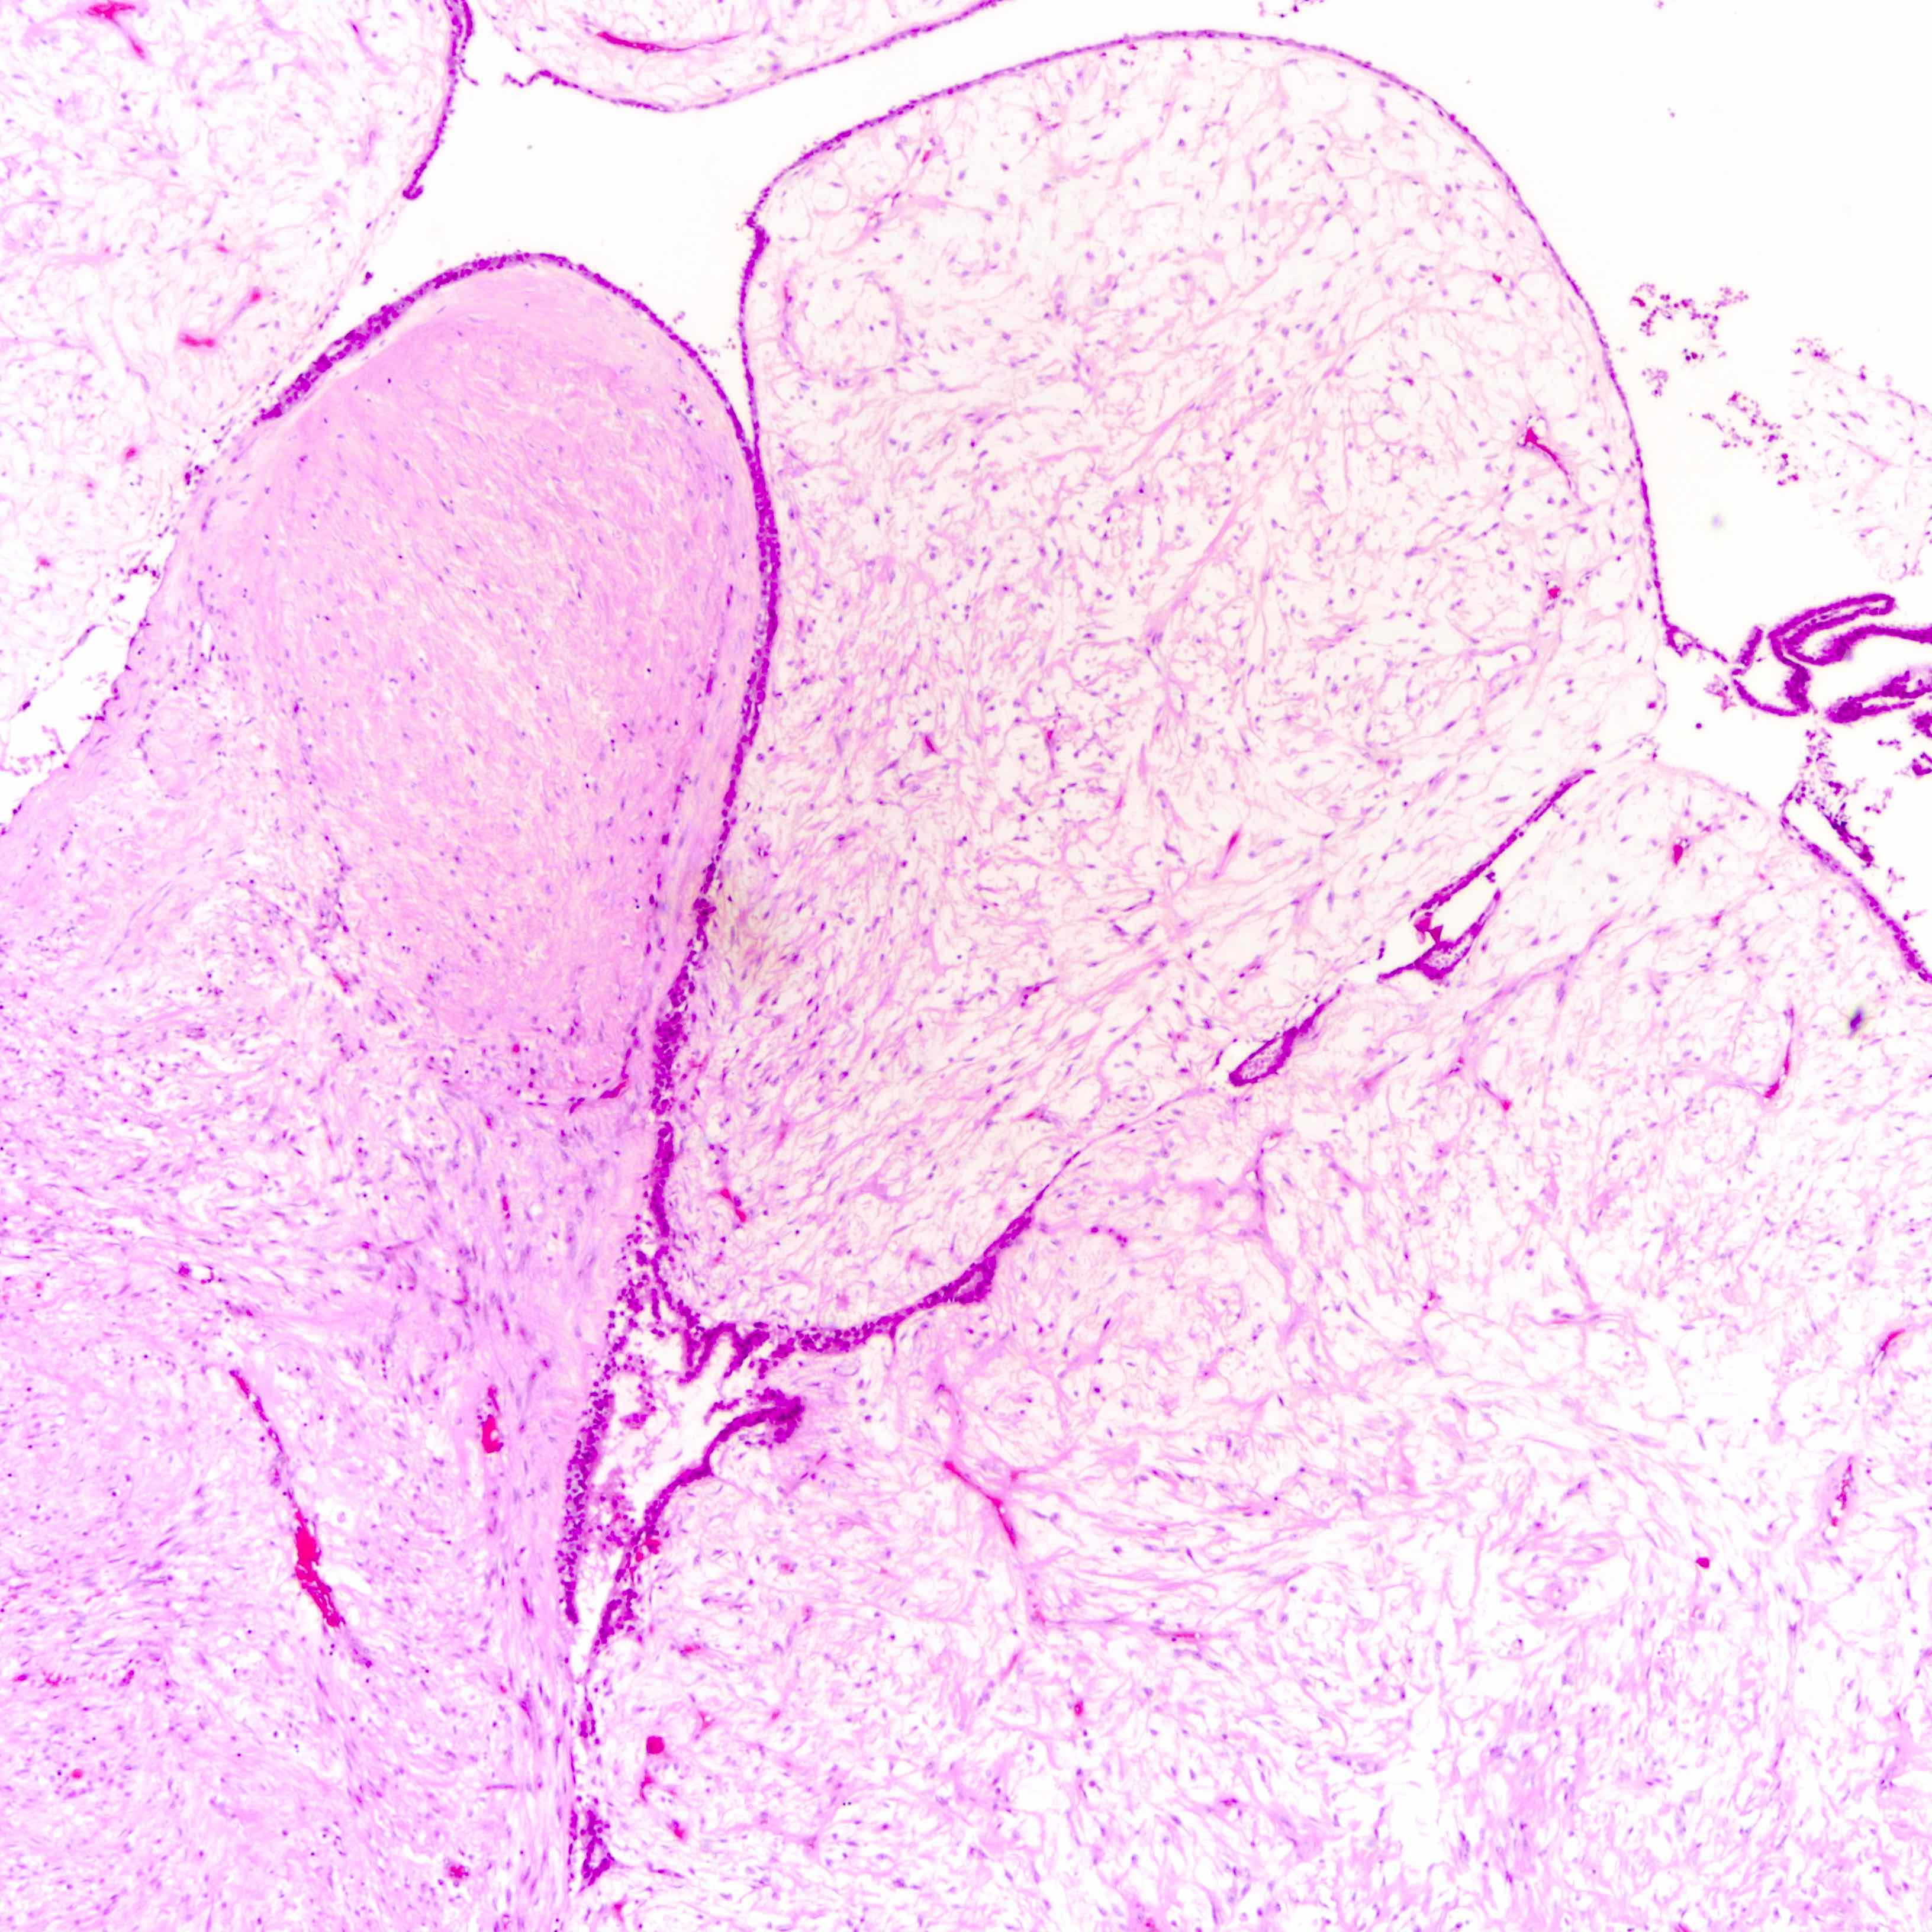

Microscopic (histologic) description

- Leaf-like (phyllodal) epithelial pattern formed by an exaggerated intracanalicular pattern

- Subepithelial condensation with increased stromal cellularity adjacent to epithelium

- Graded into benign, borderline and malignant histologic grades

Benign Borderline Malignant Stromal atypia Mild Moderate Marked Stromal cellularity Mildly increased, can be focal Moderately increased, can be focal Markedly and diffusely increased Stromal overgrowth* Absent Absent or very focal Present Mitotic count < 5/10 HPF or < 2.5/mm² 5 - 9/10 HPF or 2.5 - < 5/mm² ≥ 10/10 HPF or ≥ 5/mm² Tumor border Well defined Well defined or focally permeative Diffusely permeative Malignant heterologous elements Absent Absent Presence directly upgrades to malignant category** -

Microscopic (histologic) images

Contributed by Joshua J.X. Li, M.B.Ch.B. and Gary M. Tse, M.B.B.S.

Benign phyllodes tumor

Borderline phyllodes tumor

Malignant phyllodes tumor